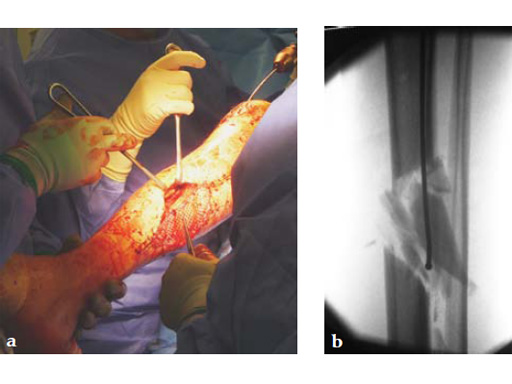

Case 1: A 33-year-old man with a third degree open fracture of his left tibia was initially treated with an external fixator and unilateral compartment release. He had undergone ACL reconstruction in the past.